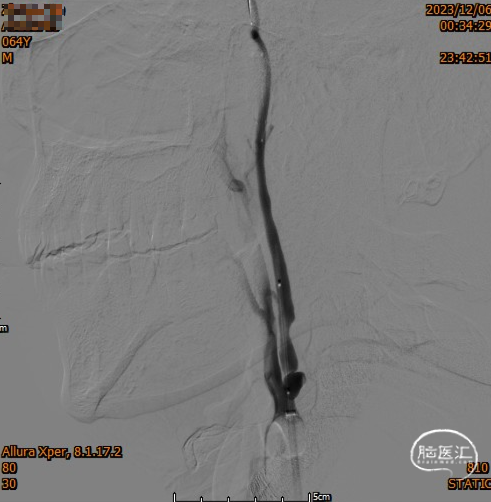

· 8F 通桥大禹™球囊导引导管到位颈总动脉末端,6F 通桥银蛇®颅内支持导管到位颈内动脉闭塞段近端;

沿着6F 通桥银蛇®颅内支持导管送入6.0mm保护伞,释放保护伞,撤出导管。沿保护伞导丝送入颈动脉球囊,行球囊预扩。

置入9.0*40mm 颈动脉支架,解除通桥大禹™球囊导引导管压力,回收保护伞,伞内可见少量脱落血栓。

复查造影支架成形良好,颅内较前无明显改变,未发现血管减少影像,供血较前明显改善。